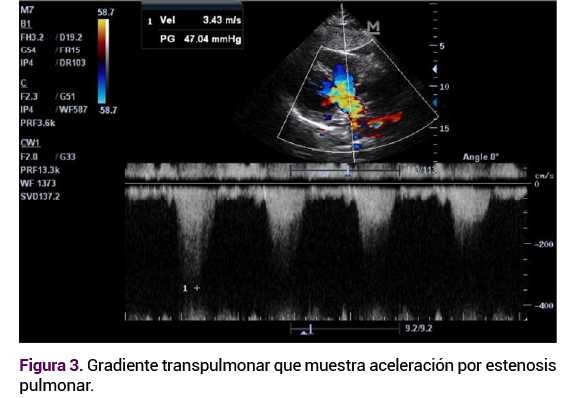

El ecocardiograma transtorácico reportó una comunicación interauricular tipo ostium secundum amplia de 27 mm (Figura 1) y comunicación interventricular subpulmonar de 15 mm (Figura 2), estenosis valvular pulmonar moderada con gradiente de 55 mmHg (Figura 3) ventrículos no dilatados, función sistólica preservada, presión sistólica ventricular ligeramente aumentada del ventrículo sistémico. Por lo anterior, se sugirió hipertensión pulmonar no grave, dextrocardia y situs inversus. Se confirmó el diagnóstico de trasposición congénitamente corregida de las grandes arterias.

Figura 3. Doppler que sugiere estenosis valvular pulmonar con gradiente elevado, en el contexto de transposición corregida.